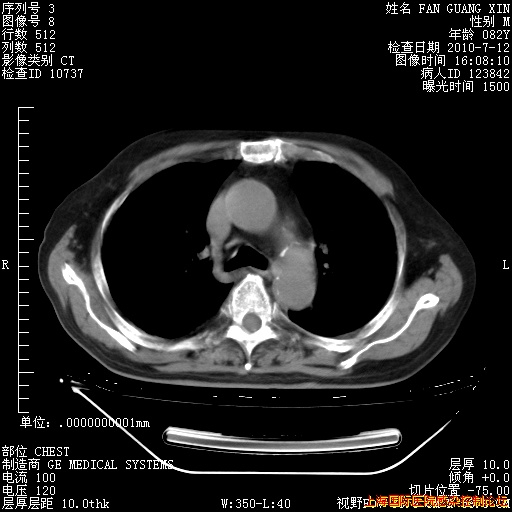

今天复查CT

今天CT

整整相隔30天的肺部CT好像有所好转啊。甲强龙减量第3天,需要观察体温。

海管,自昨日你和我通完话后,不知您岳父消化道症状有无缓解?体温怎样?阅读7.12日胸部ct,个人认为目前激素治疗是有效的,甲强龙减量是适宜的。因在抗痨治疗,需密切观察肝功、肾功能和血常规。不过,老年、长期住院和大量使用激素,很担心菌群失调发生